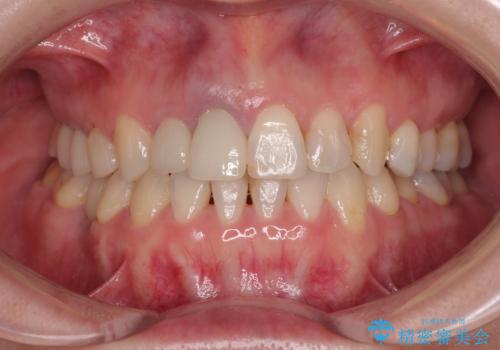

破折した前歯のインプラント 1DAYインプラントで短期間治療

前歯のインプラント治療は、従来の抜歯から数ヶ月待機する手法では、骨造成や歯肉移植など付随の処置が多く必要となり、費用、期間、身体的負担のいずれもが多大となります。

抜歯時にインプラントを埋入することでそれらの負担を大きく軽減させることが可能です。